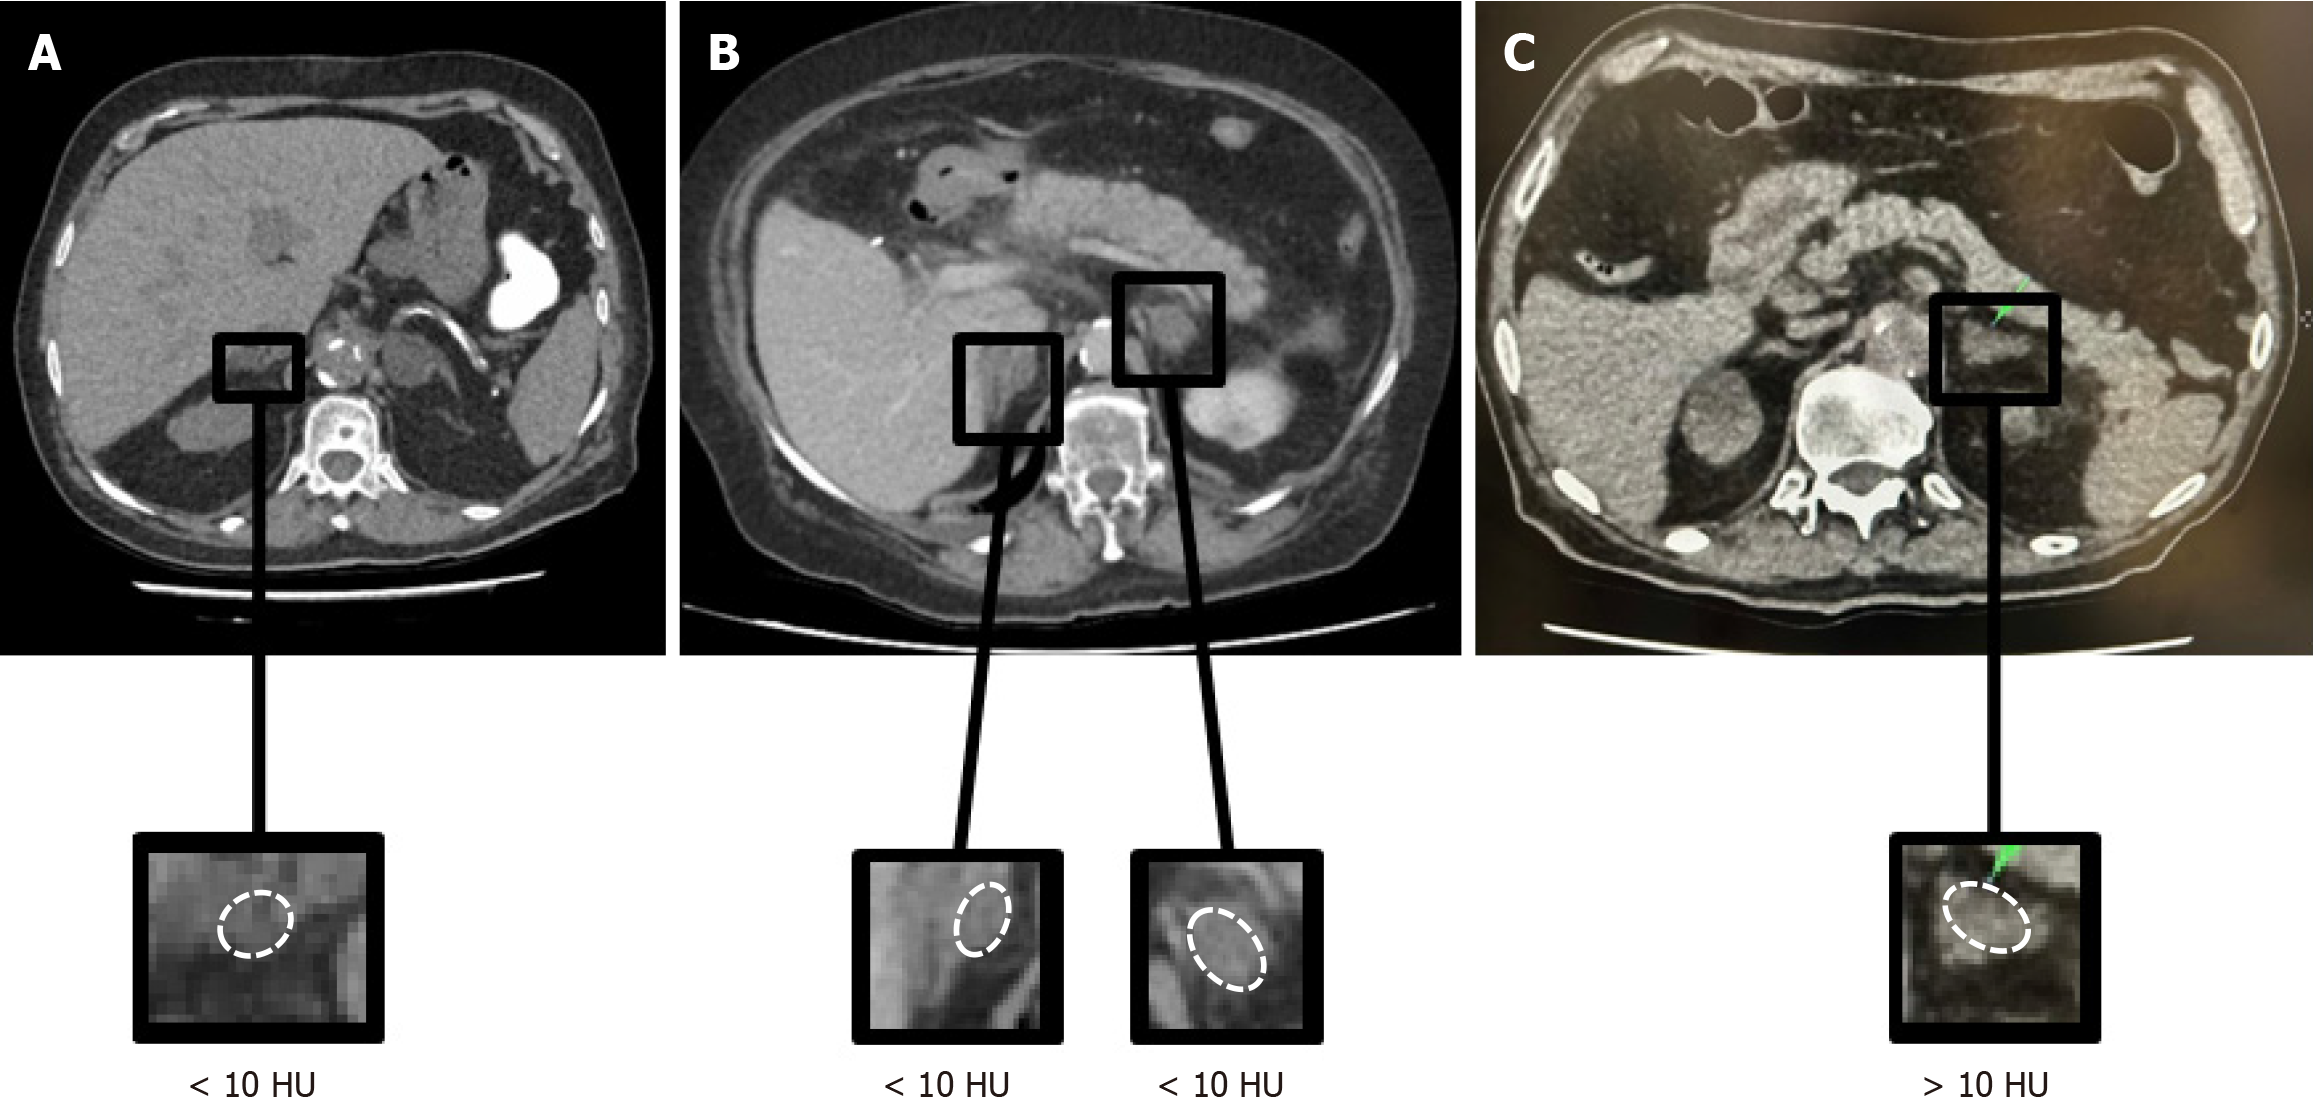

Radiological characterization represents the initial and central step in the evaluation of ADIs. The primary objective is to identify benign lipid-rich ACAs, which account for approximately 80% of ADIs in non-oncologic populations[3]. Non-contrast CT (ncCT) remains the fundamental and preferred first-line modality due to its widespread availability, reproducibility, and robust diagnostic performance[4,12,21]. The attenuation value measured in Hounsfield units (HU) on ncCT reflects tissue density and indirectly indicates intracellular lipid content, a hallmark of benign ACAs. A homogeneous adrenal mass with attenuation ≤ 10 HU is highly specific for a lipid-rich adenoma[3,12,22] (Figure 1). When this criterion is met, current ESE guidelines recommend that no further imaging follow-up is required, irrespective of lesion size, although comprehensive hormonal evaluation remains mandatory[12,22]. Thus, ncCT serves not only as a diagnostic tool but also as a triage instrument, identifying a substantial subgroup of patients in whom additional imaging surveillance can be safely avoided while maintaining vigilance through biochemical screening.

Figure 1

Figure 1 Non-contrast computed tomography is the cornerstone of imaging assessment of adrenal incidentalomas. A: Non-contrast computed tomography (ncCT) demonstrates an adrenal incidentaloma (ADI) with a density < 10 Hounsfield units (HU); B: Axial ncCT shows bilateral ADIs < 10 HU; C: Axial ncCT shows a lipid-poor left ADI with attenuation > 10 HU. HU: Hounsfield units.